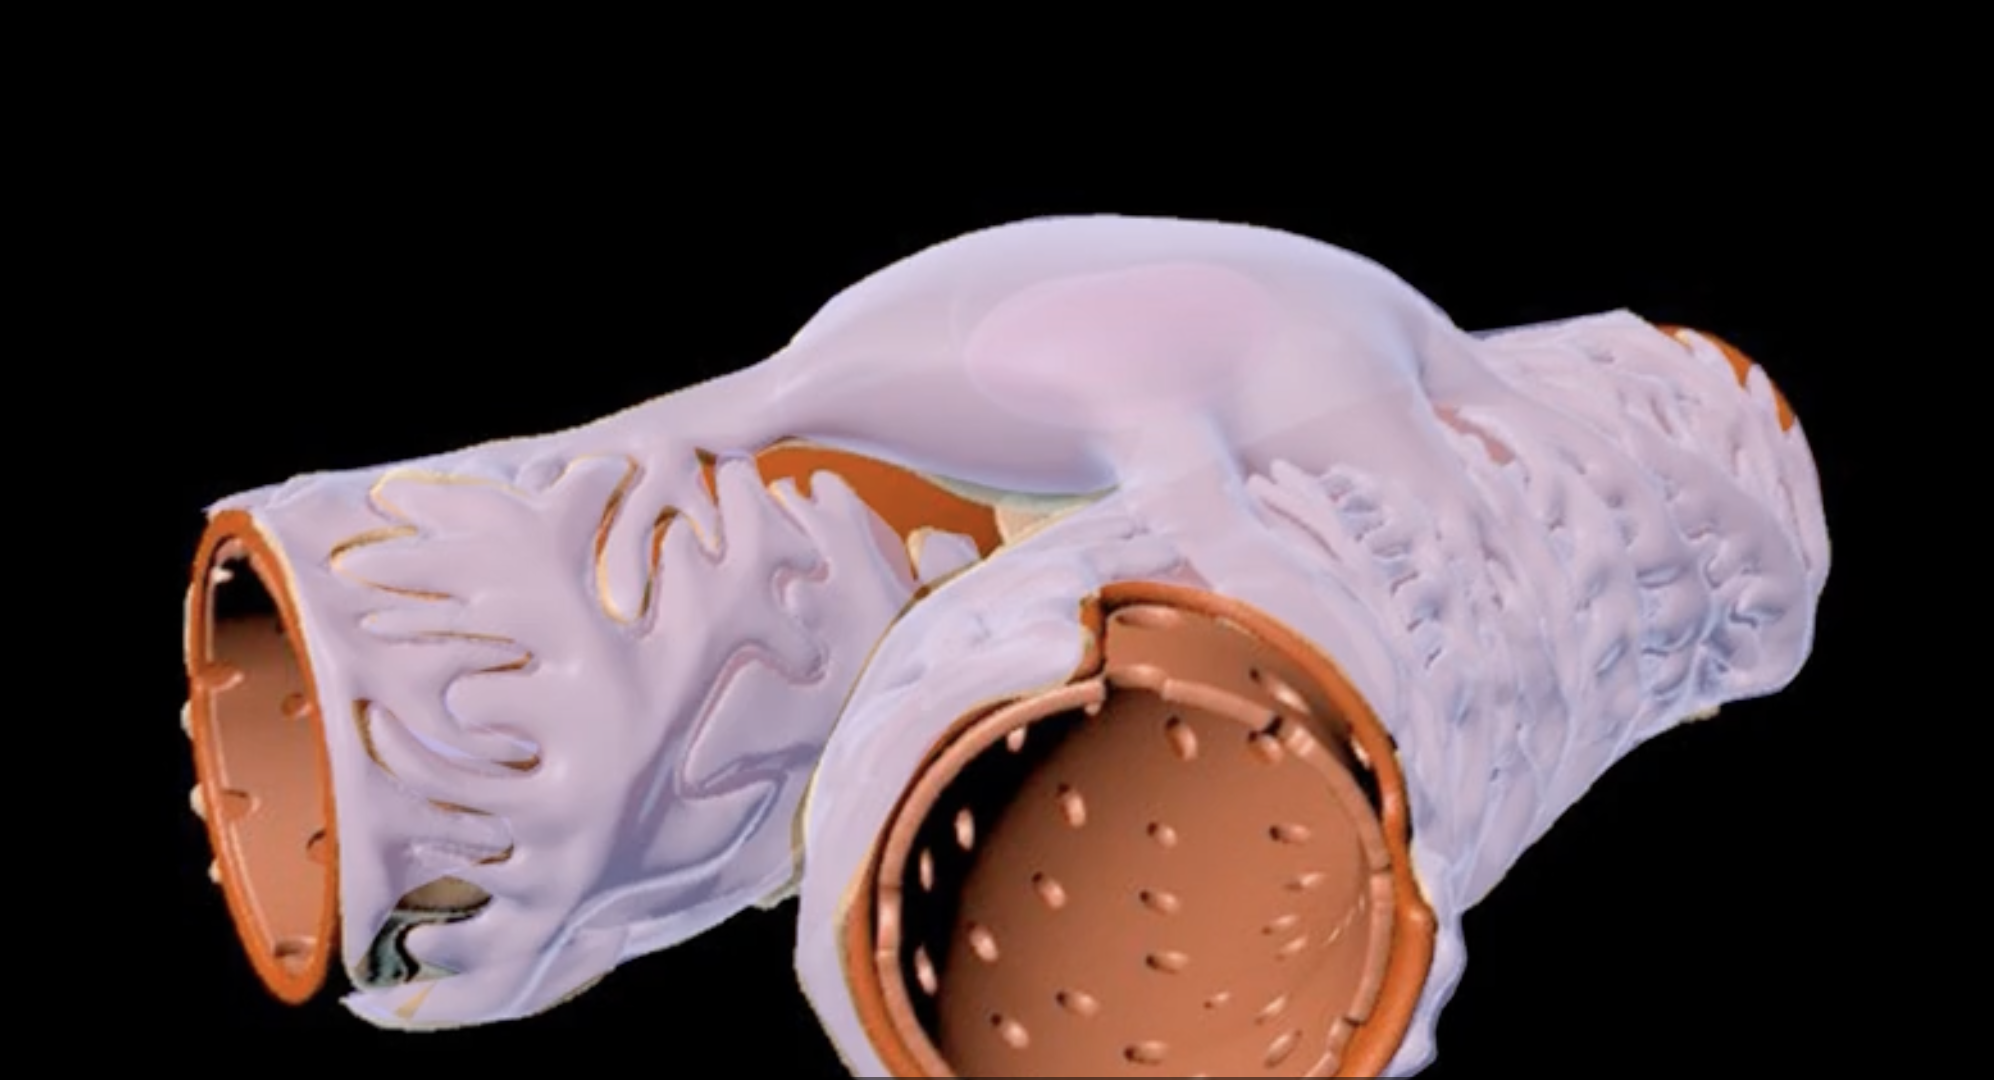

renal cortex

green

renal medulla

blue

renal columns

yellow

renal pyramids

purple

renal lobe

orange

renal papilla

minor calyx

teal

major calyces

renal pelvis

minor and major calyces